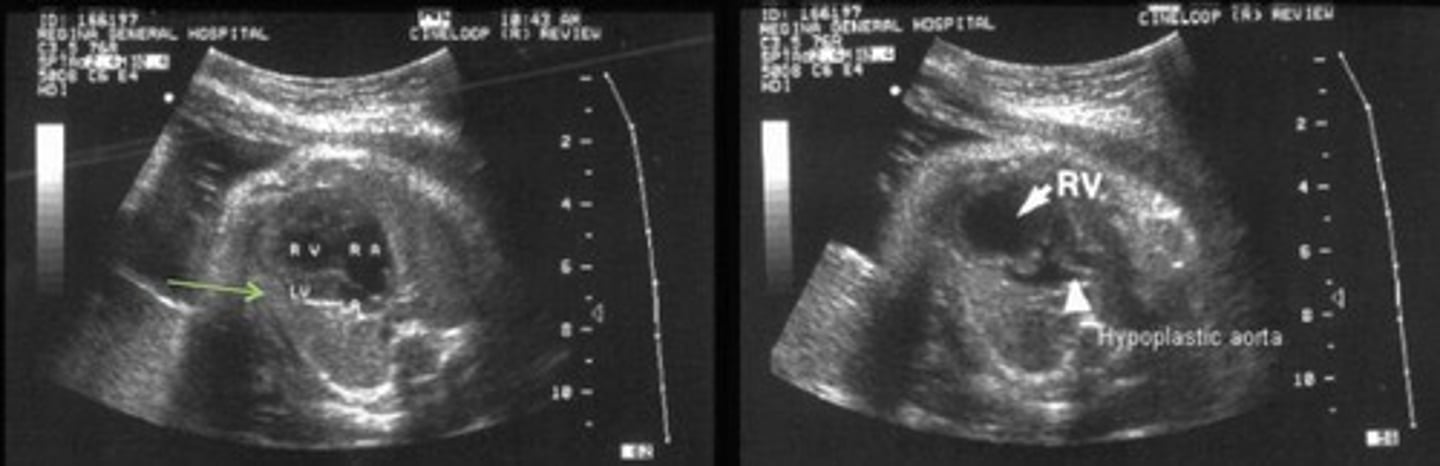

HLHS - Hypoplastic Left Heart Syndrome

Most common cause of death from heart disease during the neonatal period

Failure for LV to develop - left side of heart is small or absent

Small LV Little color flow through MV

Small AO

Reversed flow through foramen ovale and ductus arteriosus